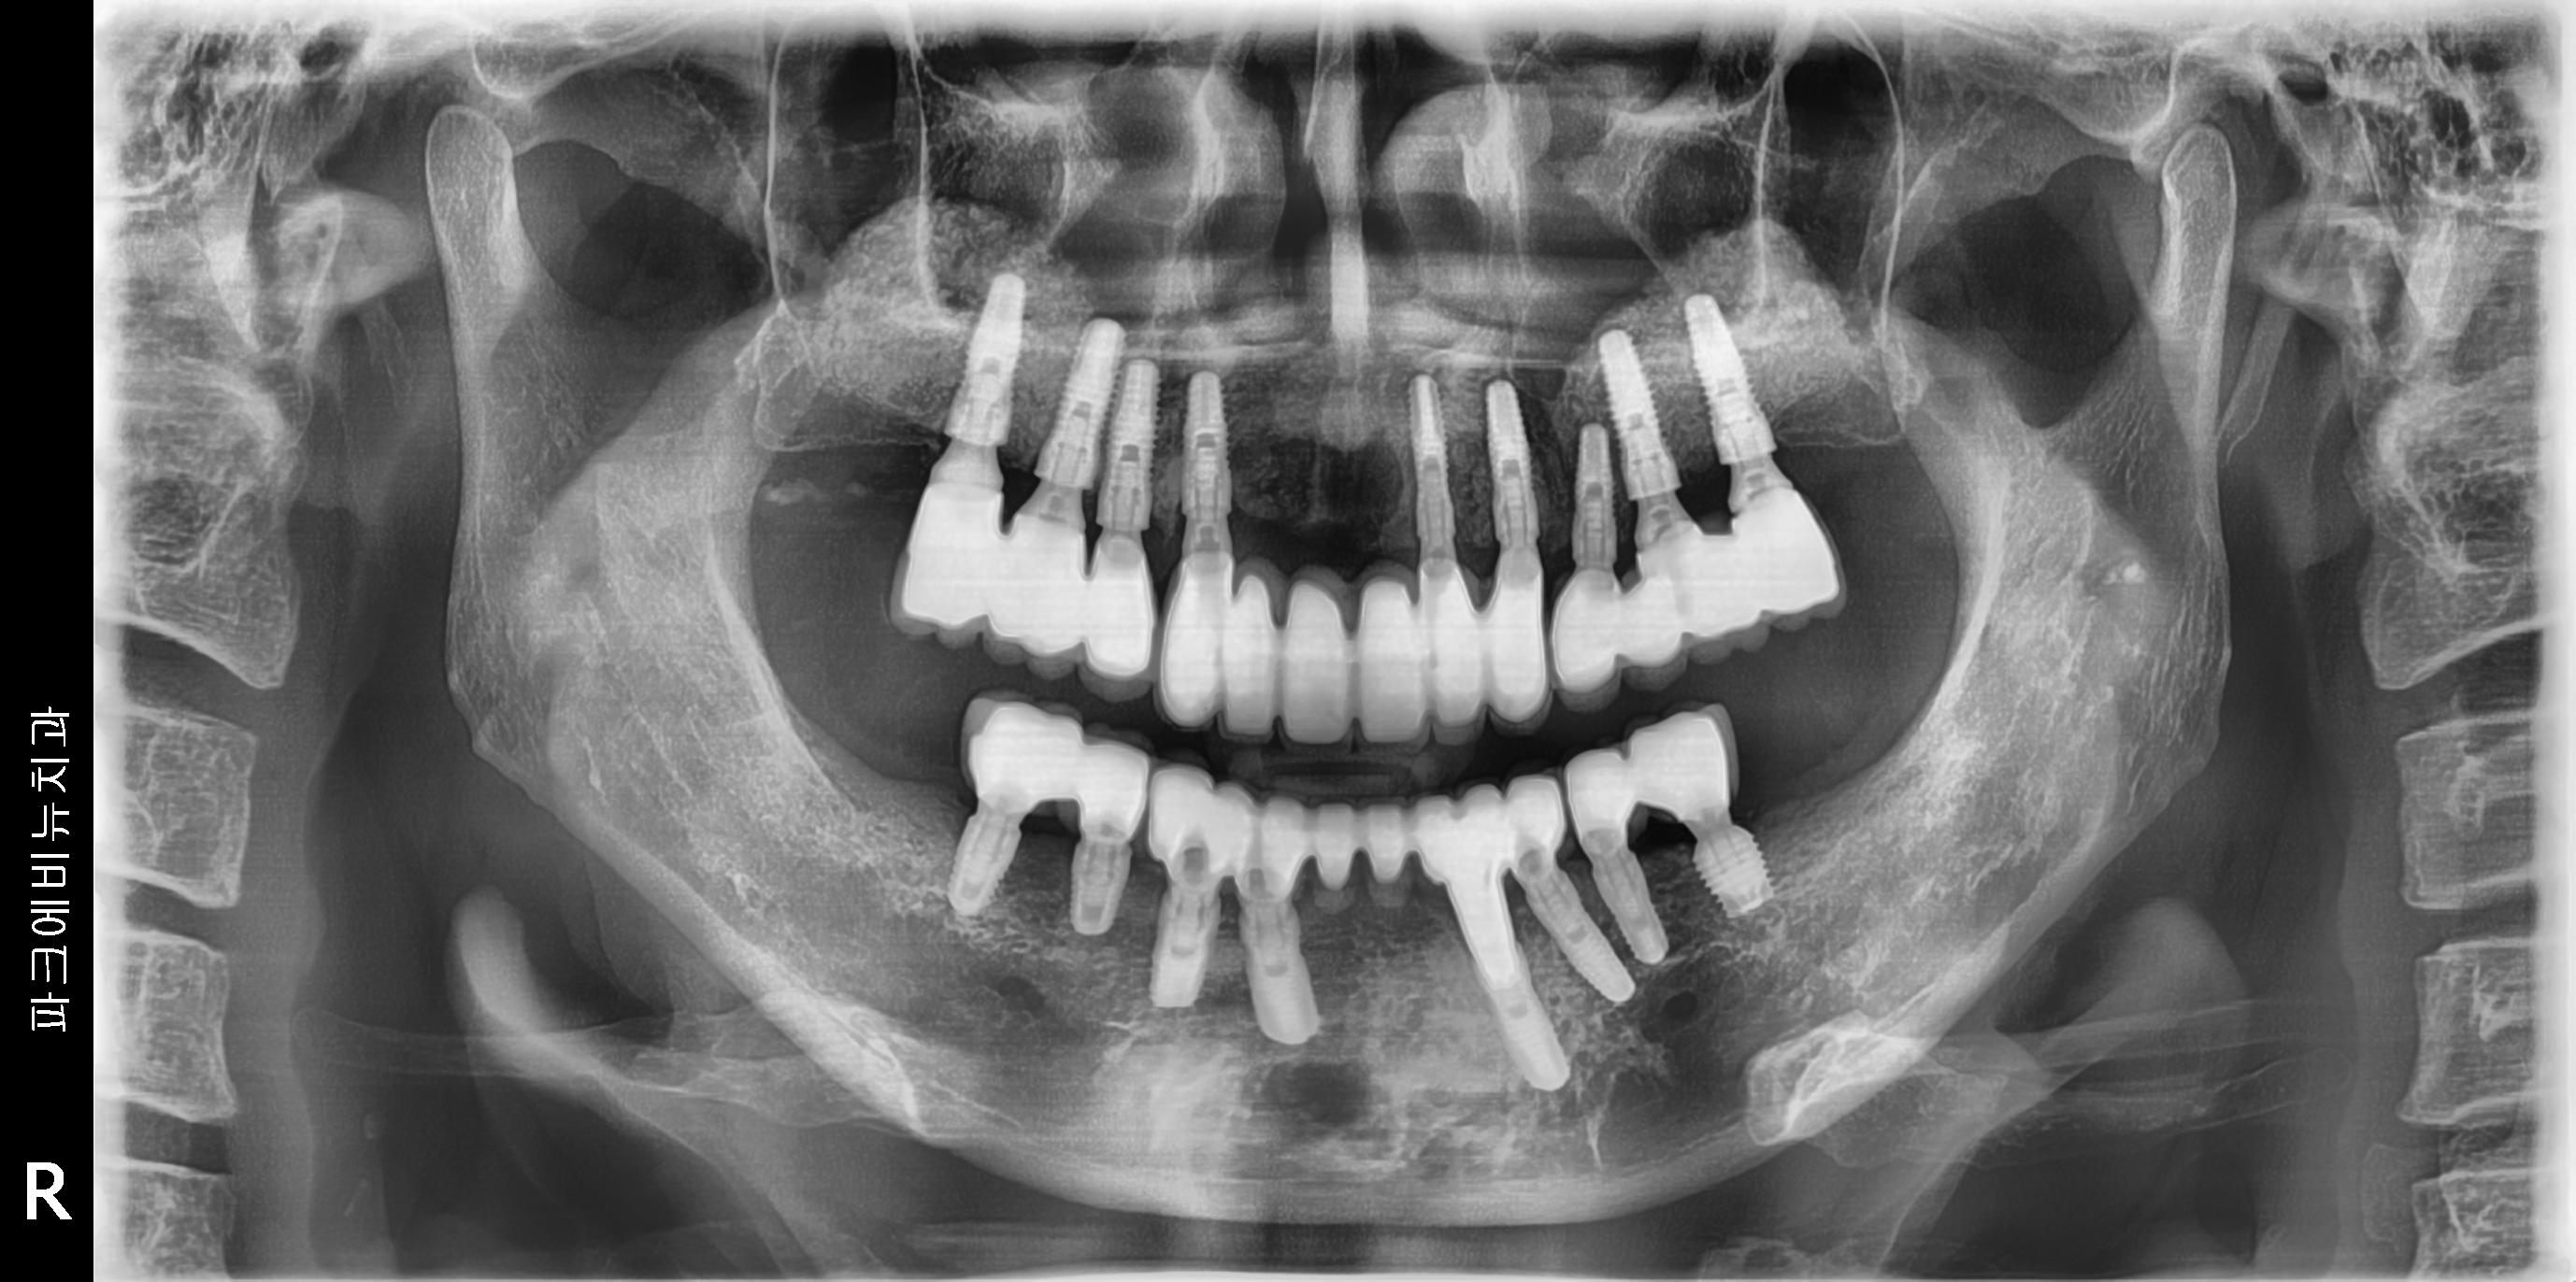

치료 중 찍은 방사선 사진입니다.

치료 필요에 따라 뼈이식도 진행하였습니다.